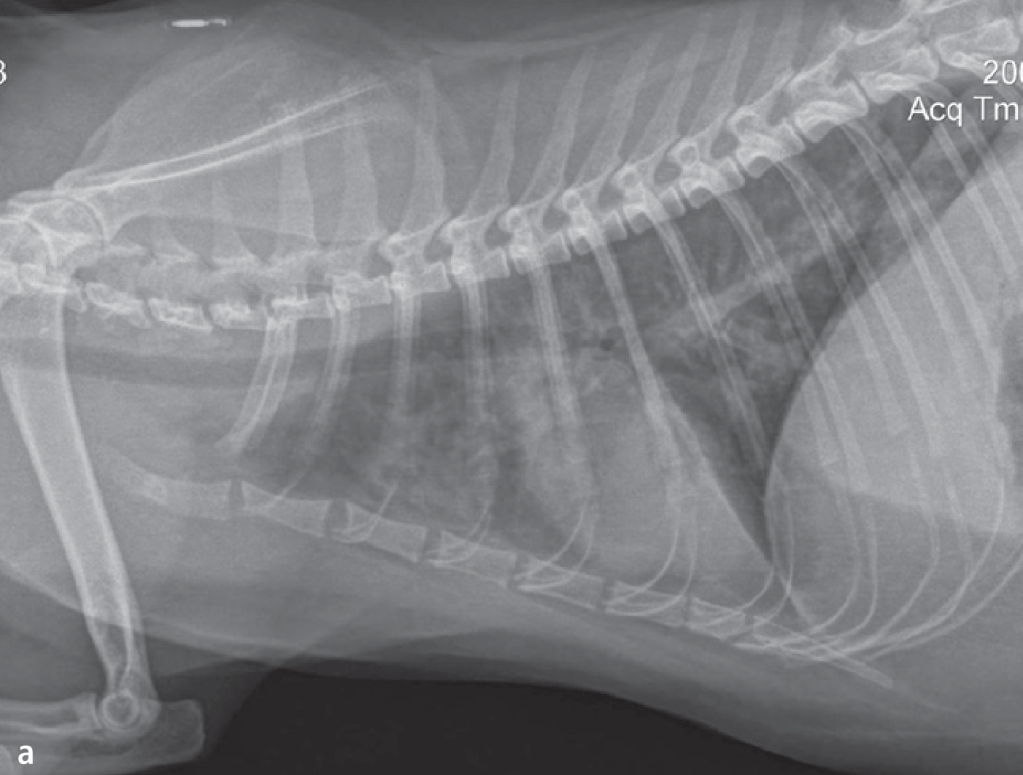

Jika pemeriksaan fisik menunjukkan adanya masalah saluran pernapasan, metode yang selanjutnya biasa dipilih adalah radiografi (x-ray) rongga dada untuk melihat ada tidaknya kelainan pada paru-paru dan jantung. Hasil radiografi akan diinterpretasikan oleh dokter hewan penanggung jawab, sehingga tidak perlu dipusingkan. Namun, sebagai gambaran, kucing yang asma bisa menunjukkan paling sering menunjukkan pola bronkhial, yaitu cincin putih atau dua garis putih seperti rel kereta api, menunjukkan adanya masalah pada bronkhus. Keanehan lain juga dapat terlihat, seperti hiperinflasi paru-paru karena kesulitan menghembuskan napas, dan kolaps lobus paru. Radiografi bisa sangat membantu mengerucutkan diagnosis, tetapi belum cukup untuk mengatakan seekor kucing kena asma. Pertama, sekitar 20% kucing dengan asma akan memiliki radiograf yang normal, sehingga radiograf yang tampak normal belum cukup untuk mengeliminasi kemungkinan asma. Kedua, radiograf asma sulit dibedakan dengan masalah bronkhus lain, seperti bronkhitis kronis karena infeksi.